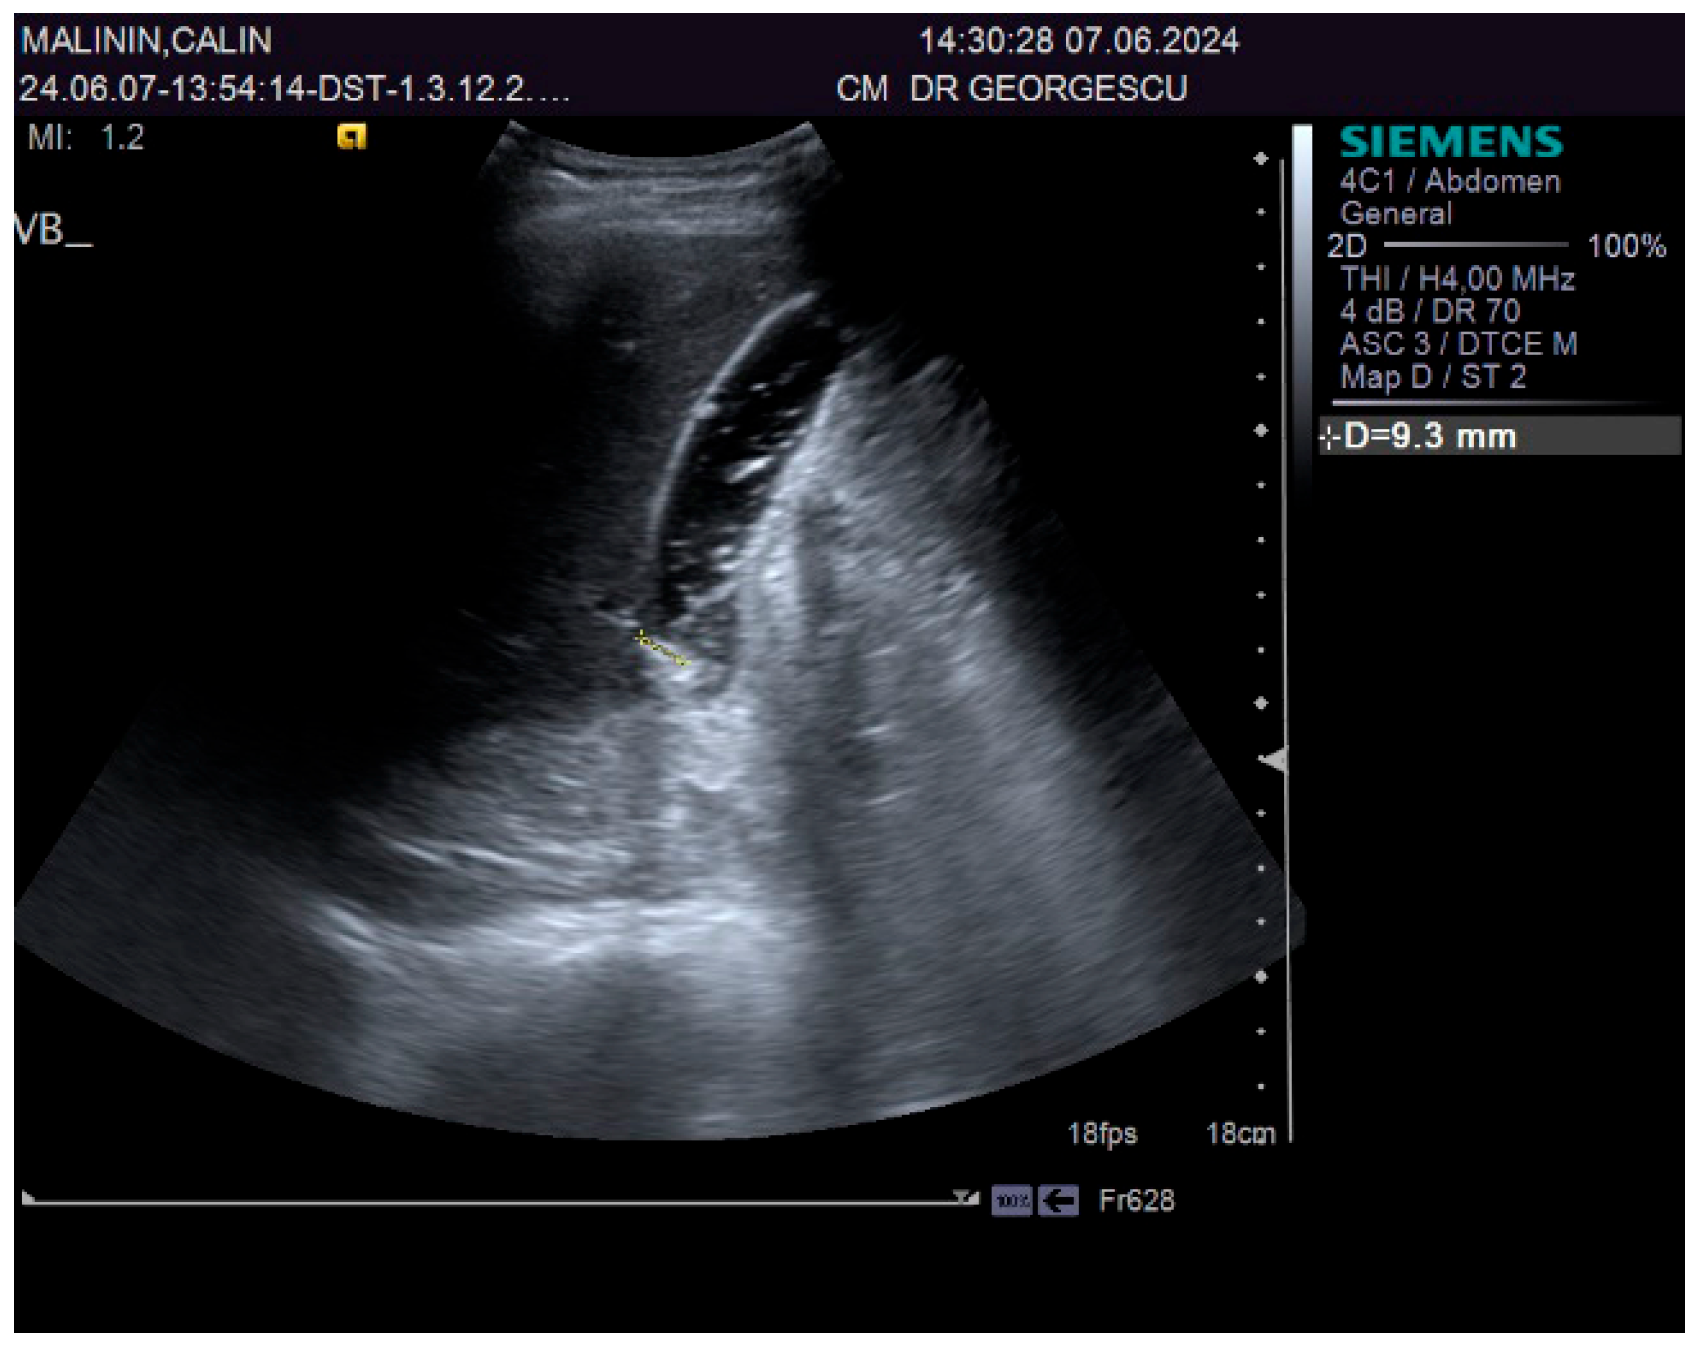

2. Case Report